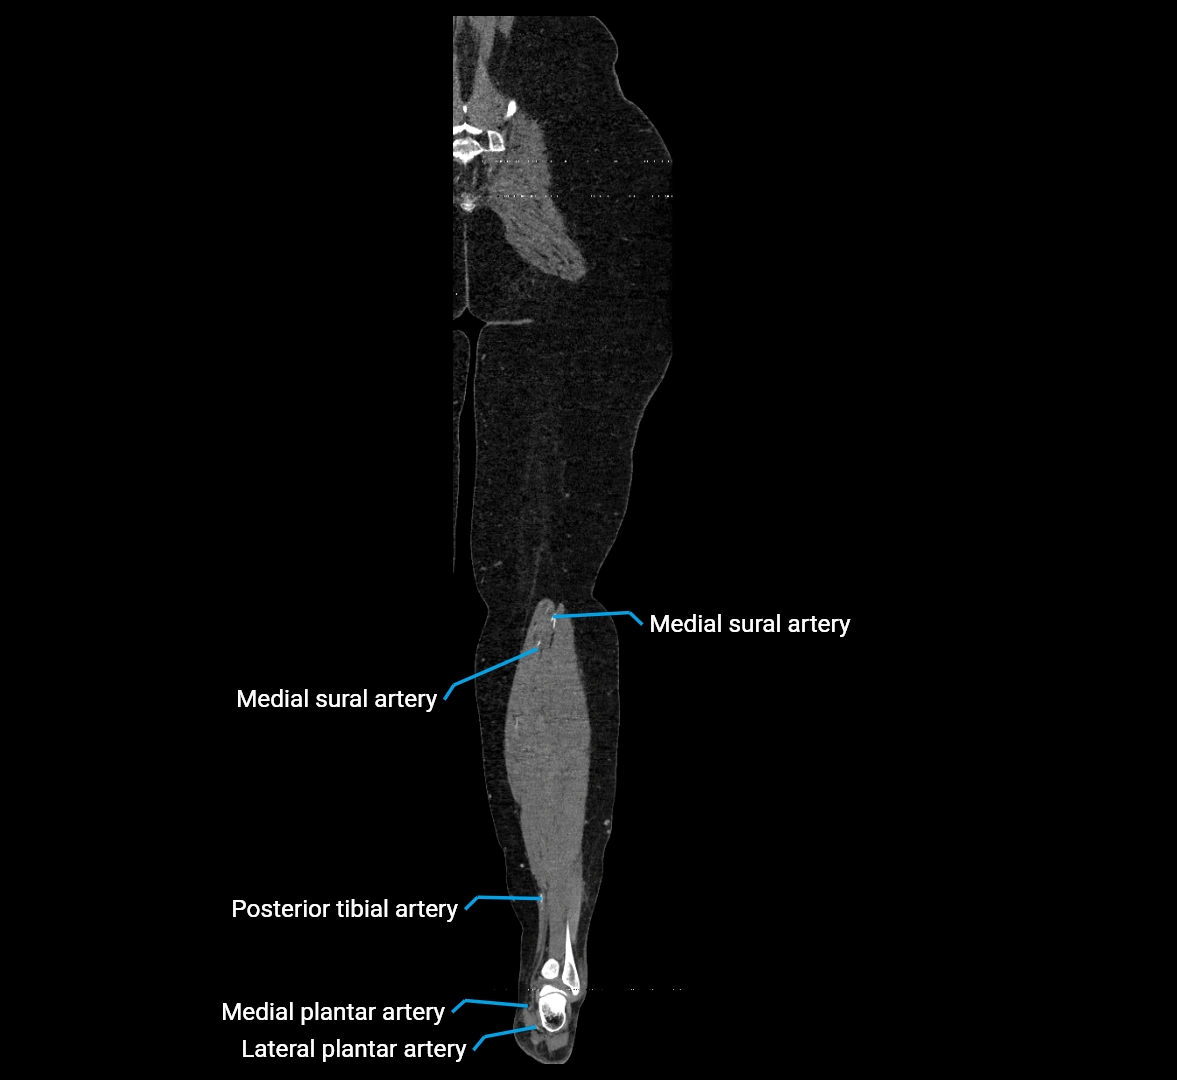

CT images

image